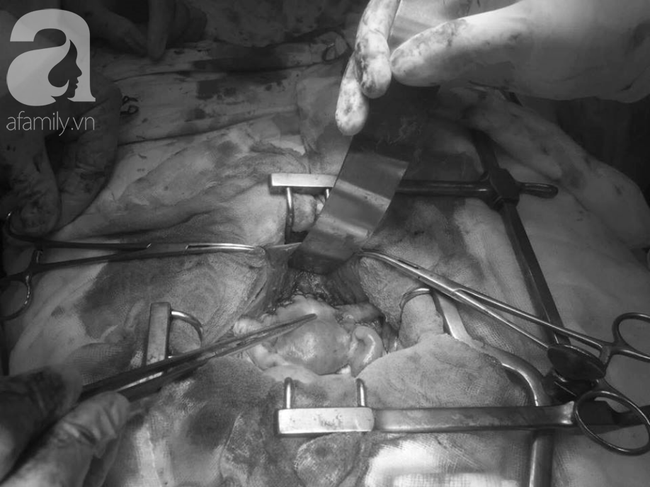

Ekip điều trị tiến hành mổ khẩn cho bệnh nhi, tuy nhiên cuộc phẫu thuật thất bại vì bướu đã xâm lấn toàn bộ tử cung, bàng quang, vách hạch chậu và hạch cạnh động mạch chủ bụng.

Ca phẫu thuật cho bé thất bại vì khối u đã xâm lấn nặng nề.